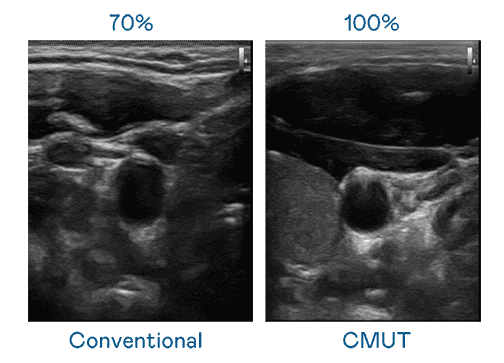

CMUT 技术是一种用电容式微机电元件来产生超音波讯号的技术。。与传统 PZT 压电式技术相比,,,,CMUT 频宽增加 30%,,,更宽频的超音波讯号让影像解析度大幅提升,,是实现高影像品质医疗超音波扫描、、、、促进精准医疗发展的关键技术。。。

大频宽带来超清晰影像

超音波影像的解析度高低,,首先取决于探头能发出的讯号频宽。。。尊龙集团 CMUT 可提供高清晰的超音波讯号,,,提供高频宽、、、高灵敏度、、、影像纹理细节更高的超音波影像,,,协助医护人员缩短影像判读时间及利用精准的医疗影像进行诊断。。。